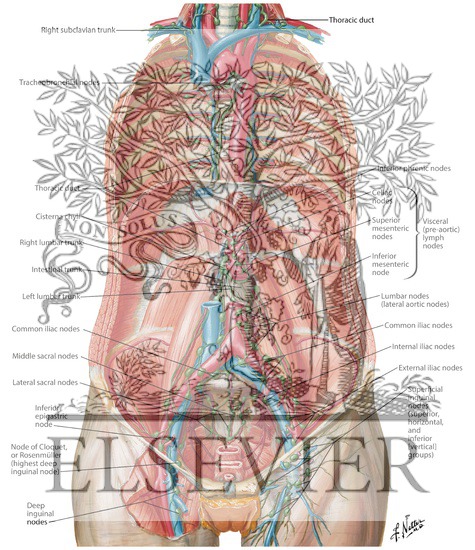

Lymph Vessels And Nodes Of Posterior Abdominal Wall

netterimages.com

netterimages.com

lymph abdominal nodes vessels wall posterior anatomy pricing